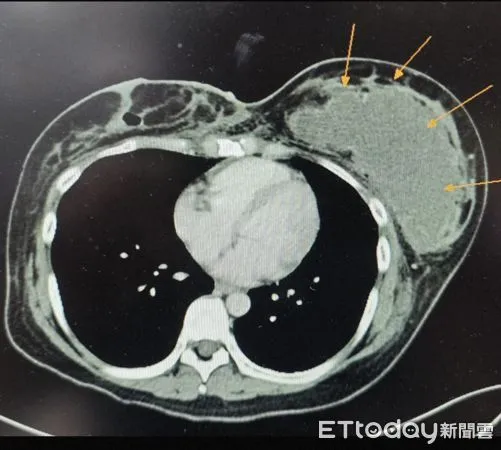

▲女子移植自體脂肪後產生巨大膿瘍,箭頭所指處為左乳病灶,另一側膿瘍已完成引流 。(圖/馬偕醫院提供)

針對此患者,尤傑銘說,病人產後為加速恢復體態,在某診所接受抽脂手術,醫師建議可將抽出的脂肪再利用、進行隆乳,本人也未表明希望升級至特定罩杯,於是醫師原則以「能補多少補多少」施打,然而術後僅1個月即出現雙側乳房紅腫熱痛等不適,經診所初步處理仍未緩解,後因劇烈胸痛、呼吸困難送馬偕急診,診斷為膿瘍合併敗血性休克,經住院接受手術引流、抗生素治療才穩定下來。

尤傑銘指出,患者本身雖已具備一定乳量,但體型中等,單側施打超過400cc脂肪已屬高風險操作,所幸感染後介入及時,並未釀成更嚴重後遺症。